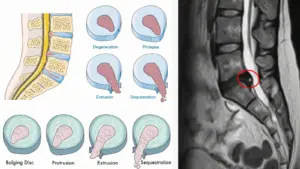

Emarda Fıtık Görüntüsü Nasıl Olur?

Fıtık tanısı en net şekilde MR (manyetik rezonans) görüntüsüyle konur.

MR’da disk, normalde yuvarlak ve düzgün görünürken fıtık varsa dışarı doğru taşmış, sinire doğru itilmiş bir şekilde çıkar. Bazı hastalar “MR’da fıtık var dediler ama ben ağrı hissetmiyorum” diyebilir. Bu durumda fıtık henüz sinire baskı yapmamıştır. Yani görüntü vardır ama belirti yoktur.

Bu da bize şunu gösterir: Fıtık nasıl anlaşılır sorusunun tek yanıtı MR değildir, çünkü bazen klinik bulgular (yani senin hissettiklerin) görüntüden daha belirleyicidir.